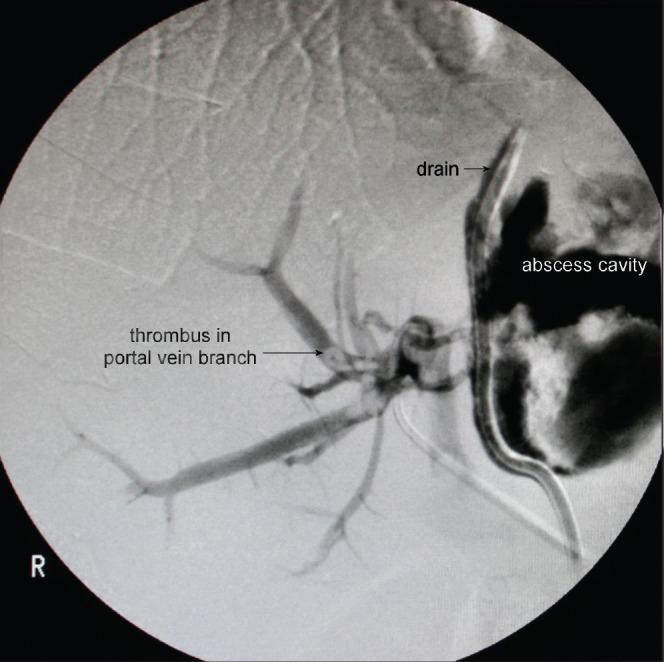

Pseudocyst formation following acute and chronic pancreatitis is a well known complication. A pancreatic pseudocyst fistulating into the portal vein is a rare and potentially fatal complication. We report a case of pancreatic pseudocyst - portal vein fistula, which was managed with a conservative approach.

急性和慢性胰腺炎后形成假性囊肿是一种众所周知的并发症。胰腺假性囊肿向门静脉内破溃是一种罕见且可能致命的并发症。我们报告一例胰腺假性囊肿 - 门静脉瘘病例,该病例采用保守方法治疗。